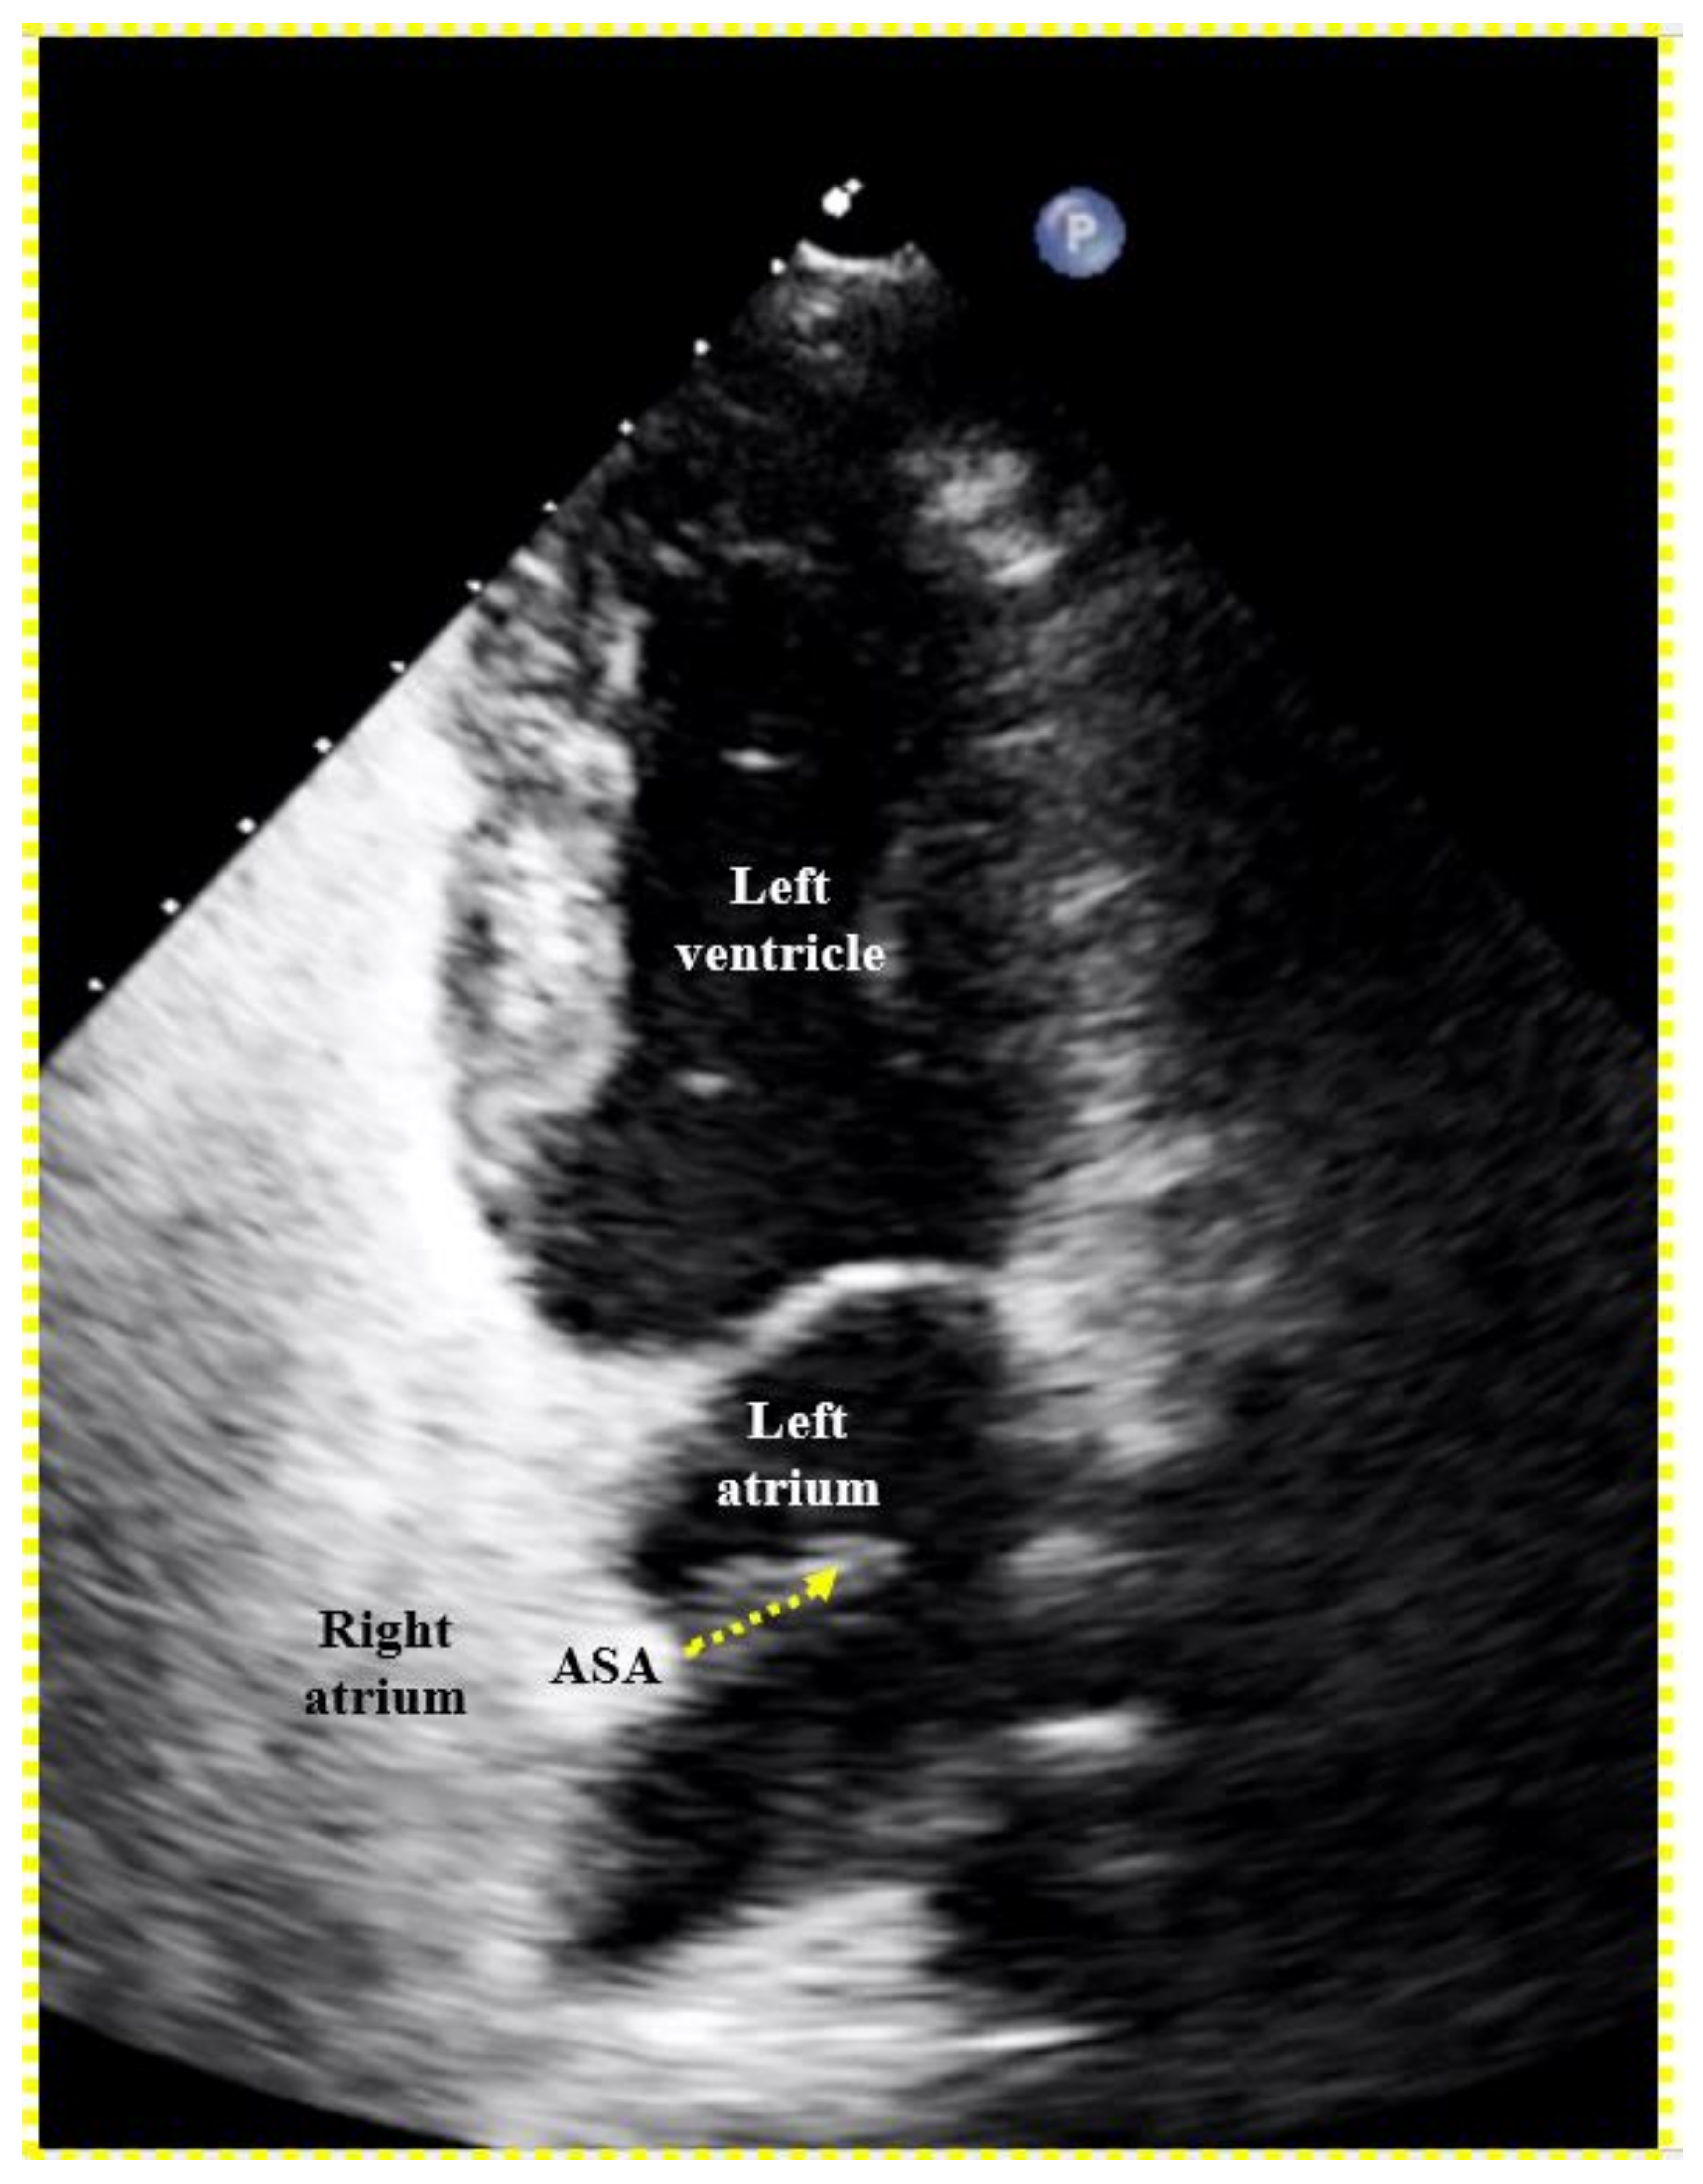

To screen for dangerous PFOs, i.e., large ones or those associated with an ASA,8 a Eustachian valve,9–12 or a Chiari network,13 a bubble test during a TTE suffices (Figure 5). The contrast liquid has to be injected at the end of a sustained Valsalva maneuver. A Valsalva maneuver or pressing into the belly by a medical person during TEE if a sedated patient cannot perform a Valsalva maneuver, blocks the backflow of the venous blood into the thorax. Both atria get volume depleted within 10 to 20 s. Upon Valsalva release, the venous blood gushes into the right atrium first, thereby pushing the PFO open towards the still underfilled left atrium.

Figure 5. Proof of a patent foramen ovale (PFO) with right-to-left shunt with transthoracic echocardiography. A right-to-left bubble shunt (dotted arrow) is demonstrated with its origin in the region of a conspicuous atrial septal aneurysm (ASA).